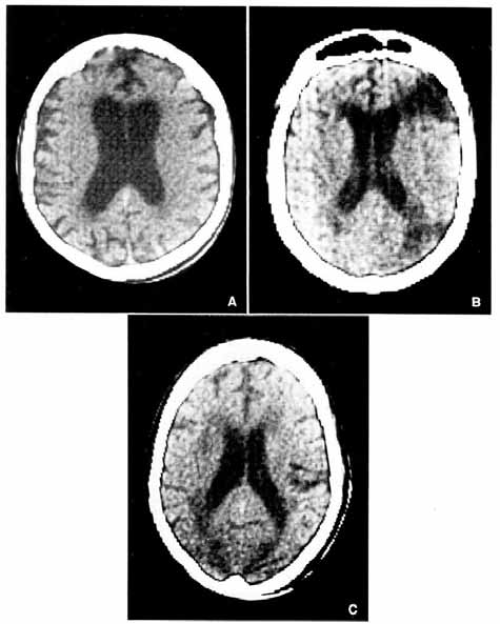

Kompjuterizovana tomografija mozga:

1. Senilna demencija Alzheimer-o- vog tipa, sa atrofijom frontalnih lobusa i proširenjem interfemisferične fisure uz simetričnu dilataciju lateralnih moždanih komora,

2. Multiinfarktna demencija bez znakova atrofije mozga, ali sa dve zone ishemične infarkcije u graničnim predelima (water- shed), između prednje i srednje cerebralne arterije, kao i između zadnje i srednje cerebralne arterije,

3. Binswanger-ova subkortikalna arteri- osklerotična encefalopatija sa tipičnim znacima subkortikalne atrofije.